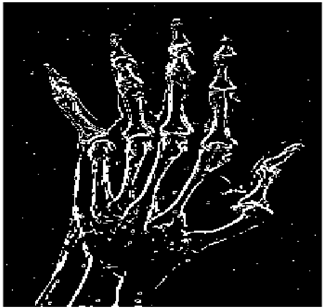

Table 13. Edge-detected image of “X-ray 4” after binarization for different noises.

NoiseCannyStandardSmooth

No noise Mathematics 10 02421 i135 Mathematics 10 02421 i136 Mathematics 10 02421 i137

G(0.001) Mathematics 10 02421 i138 Mathematics 10 02421 i139 Mathematics 10 02421 i140

G(0.002) Mathematics 10 02421 i141 Mathematics 10 02421 i142 Mathematics 10 02421 i143

G(0.003) Mathematics 10 02421 i144 Mathematics 10 02421 i145 Mathematics 10 02421 i146

I(0.25%) Mathematics 10 02421 i147 Mathematics 10 02421 i148 Mathematics 10 02421 i149

I(0.5%) Mathematics 10 02421 i150 Mathematics 10 02421 i151 Mathematics 10 02421 i152

I(1%) Mathematics 10 02421 i153 Mathematics 10 02421 i154 Mathematics 10 02421 i155

For Table 11, Table 12 and Table 13, the same points of Table 10 can be made. Therefore, for the sake of brevity, the points are not mentioned.